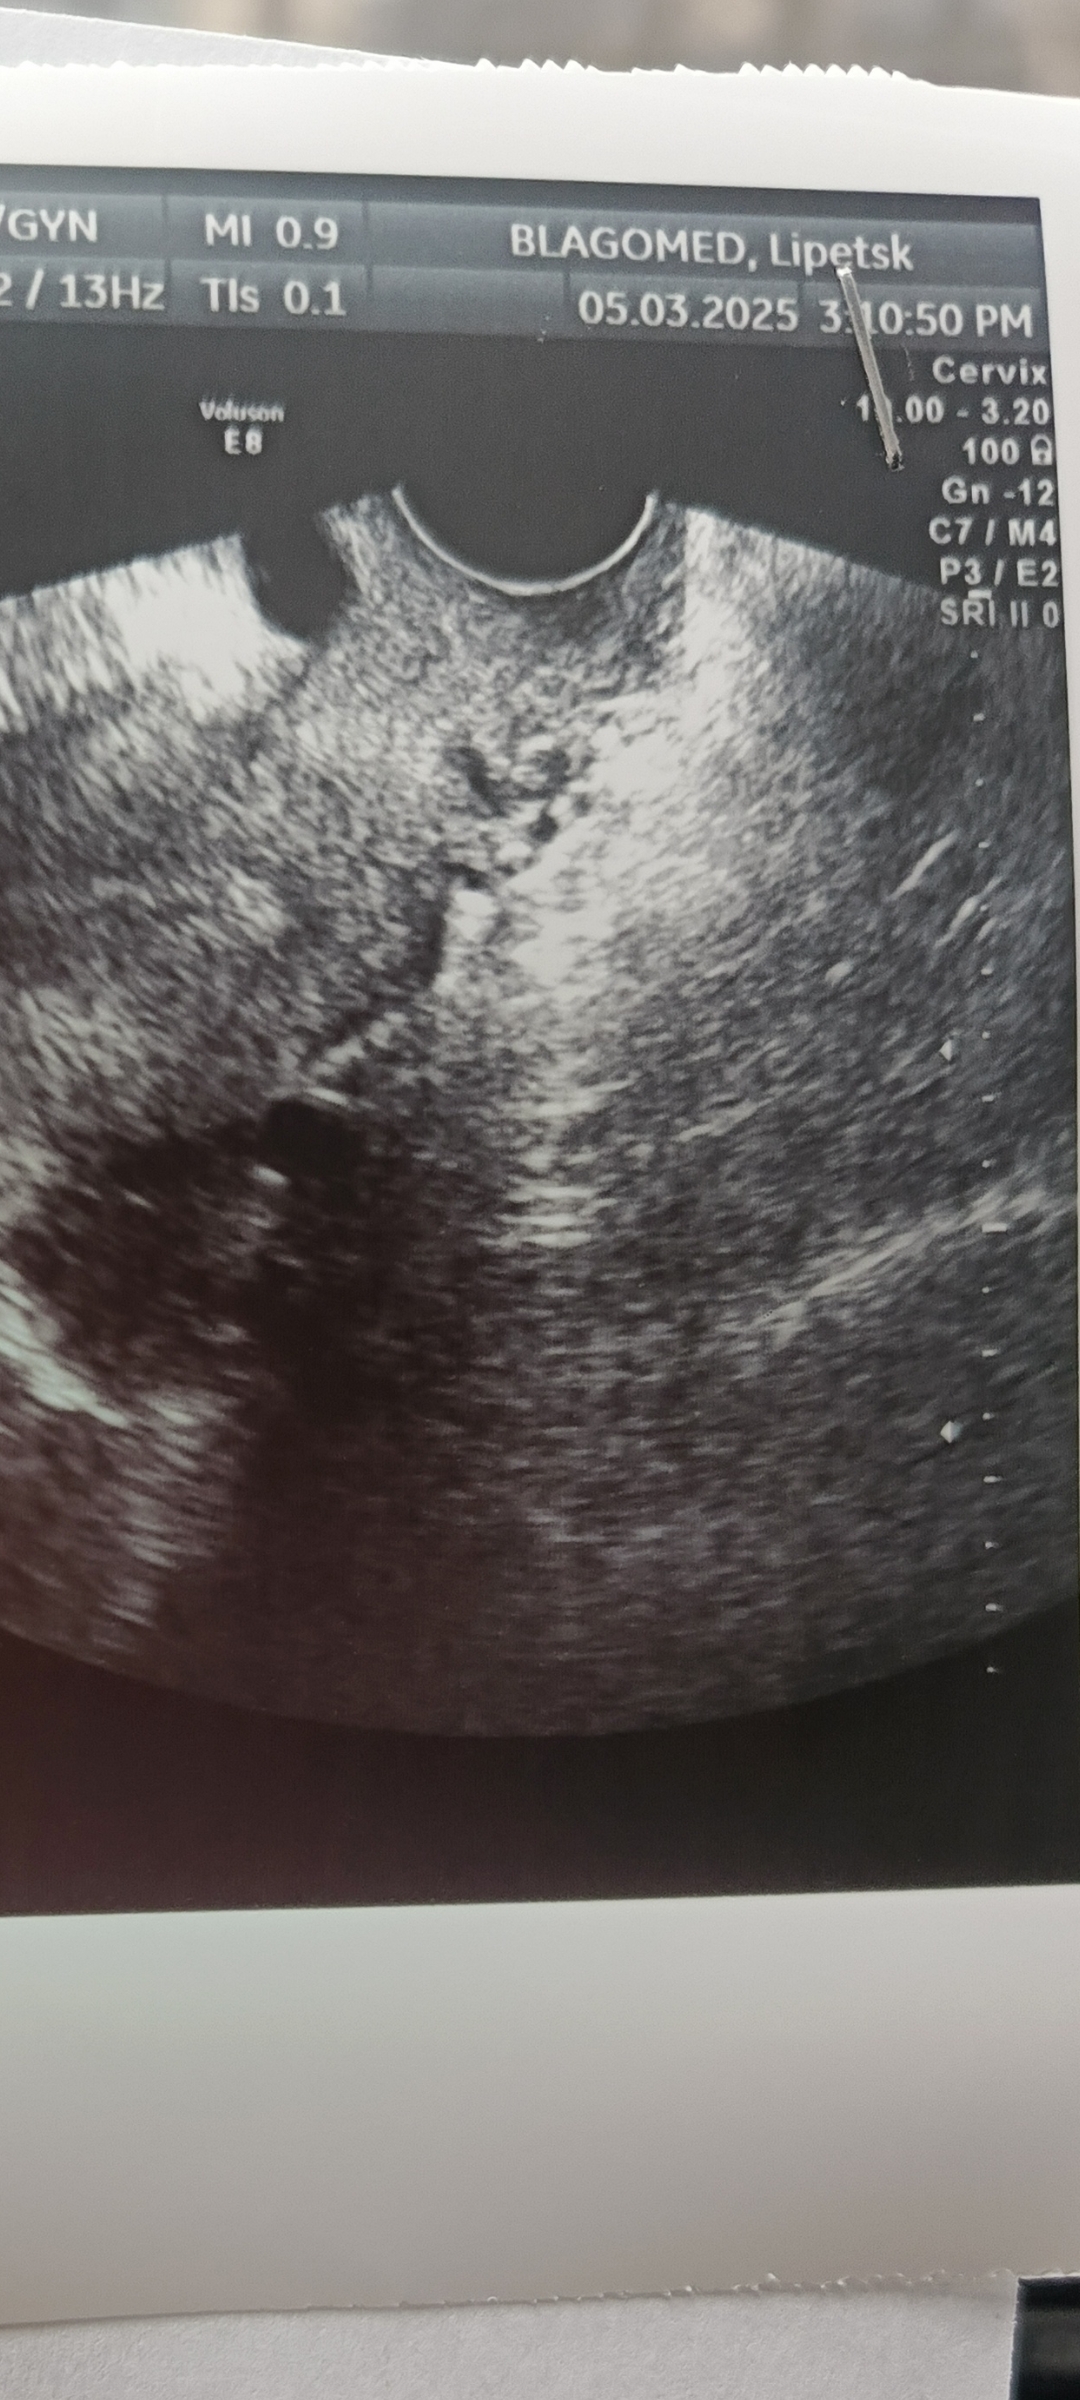

Девочки а что за кружки на узи с права? Не может быть беременность?

Если бы была беременность, то вам написали бы в заключении. Скорее всего фолликул.

Мне вчера тоже так показала, в матке черное пятно было

Виктория , (маточная беременность малого срока?) в заключении вот так было написано

Фолликулы, скорее всего

Виктория , для врача снимки неинформативны, он будет читать заключение, так могут выглядеть и сосуды, и кисты, и плодное яйцо, по фотографии гадать он не будет.